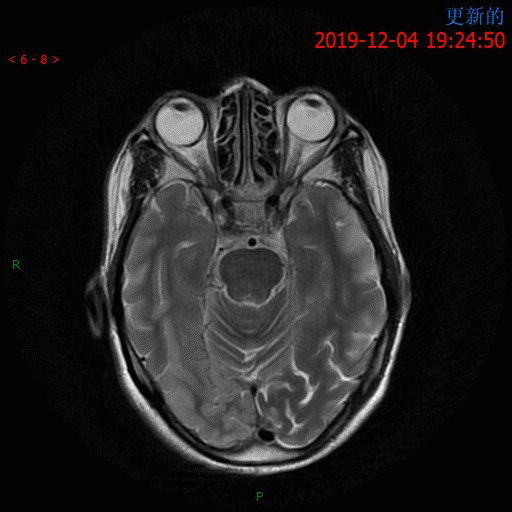

12.4 日 MR 平扫

患者为中年女性,临床症状不重,影像表现明显。双侧大脑半球多发病变,DWI 呈高信号,呈非对称性分布,且病灶分布呈跨血管支配区分布,DSA 为正常表现,可以排除脑梗死。短期内病灶迅速进展,MRS 可以看到明显倒置的乳酸双峰,考虑 MELAS。